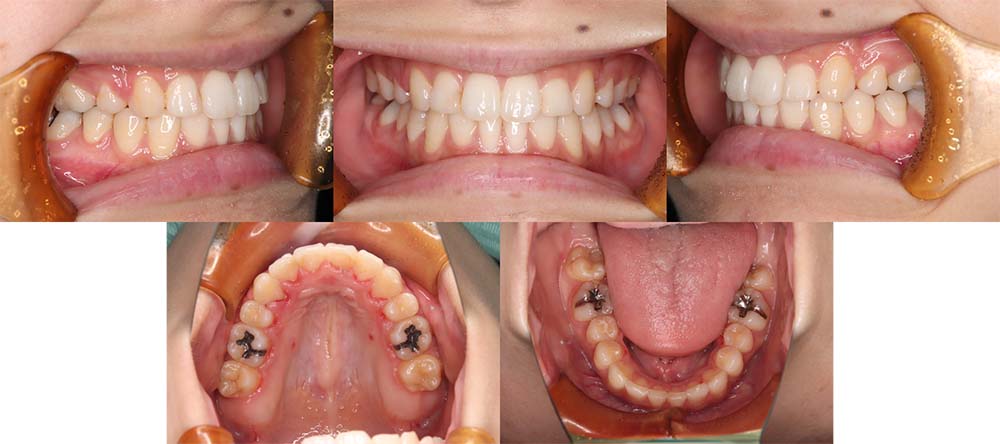

| 症例分類 | 上顎前突、口唇突出 |

| 診断名 | 左下4先天欠損を伴う上下前歯部叢生と骨格性上顎前突 |

| 主訴 | 出っ歯、下の歯がガタガタ、乳歯が1本ある |

| 年齢 | 31歳4ヶ月 |

| 性別 | 女性 |

| 抜歯部位 | 上の左右第一小臼歯と右下第二小臼歯と左下第二乳臼歯(4本) |

| 使用装置 | 上下裏側のワイヤー装置 |

| 治療期間 | 2年9ヶ月 |

| 保定装置 | 固定式保定装置、取り外し式保定装置(8時間) |

| 費用 |

[検査・診断料] ¥49,500 [基本施術料] ¥1,331,000 [調整料] ¥5,500/回 [抜歯] ¥5,500/本 [保定装置] ¥55,000(税込) 抜歯や虫歯治療は他院にて費用が別途かかります。(抜歯¥4,000〜10,000/本)

左下の永久歯が先天欠損で子供の歯が残っていて、その歯が抜けそうになったこともあり、矯正治療を考えて来院されました。

上下叢生と口唇閉鎖不全のため上下の抜歯をして治療をしました。下顎左側乳歯を抜去して治療をしました。

歯の動きが少しゆっくりだったため、予定より治療期間が伸びてしまいましたが問題なく咬合させることができました。